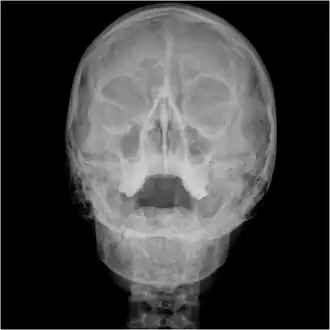

| .tif.jpg) Waters view showing diffuse prominent mucosal thickening in the right maxillary sinus and mild nmucosal thickening in the left maxillary sinus. | |

Orbital x-ray or orbital radiography is an x-ray of both left and right eye sockets, to include the Frontal Sinuses and Maxillary Sinuses.

An orbital x-ray usually requires only one view unless the requester is looking for evidence of metallic fragments, in which case two projections can be made. One with the eyes looking up, one with the eyes looking down. These views will show any movement of fragments and helps rule out false positives / artefacts which may be present on the image receiver. Two other important views are the Water's view which helps visualise the anterior orbital floor and maxillary sinuses; and the Caldwell view which helps to visualise the frontal and ethmoid sinuses and posterior orbital floor.[3]